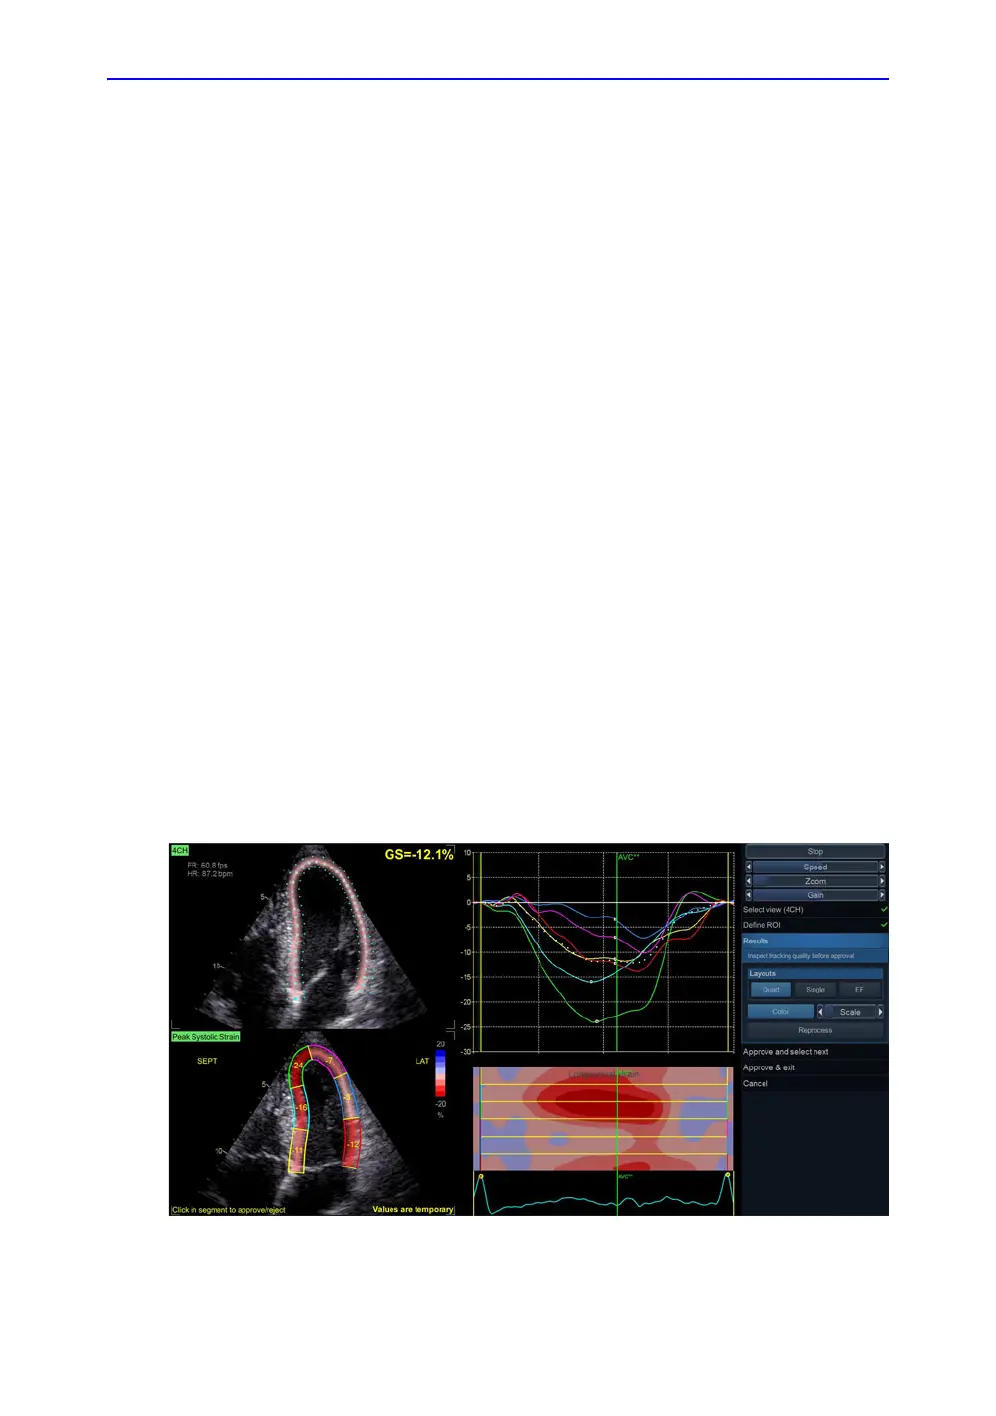

5. The AFI tool is now displaying the Results stage in a Quad

layout. Now the tracking quality must be inspected and

verified. The tracked ROI is divided into segments. The

tracking quality for each segment is automatically evaluated

and applied to reject segments for which the tracking is

assumed to be not reliable. Segments that have been

rejected do not have values in the segmental result ROI to

the lower left in the Quad view, but instead shows an X. The

strain trace (upper right), Curved Anatomic M-mode section

(lower right) and parametric overlay on the dynamic ROI

(upper left) are disabled for rejected segments. By clicking

on a segment in the segmental result ROI it is possible to

override the automatic quality assessment to either show or

hide segmental values. The tracking for each segment must

be visually controlled and validated as described below.

Figure 8-13. Results stage in Quad layout